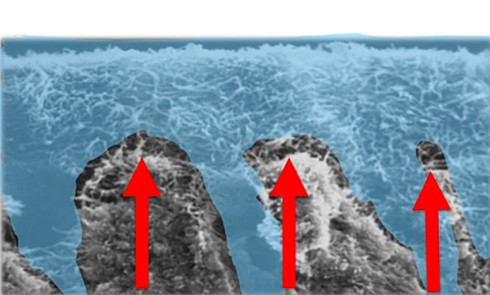

Le principe d’érosion infiltration consiste à infiltrer par capillarité l’émail déminéralisé avec de la résine. La surface dentaire doit être préalablement traitée par un acide afin d’ouvrir les porosités de surface de l’émail et permettre une meilleure pénétration de la résine. Le processus carieux sera stoppé en bloquant la pénétration des acides cariogènes et la structure dentaire sera préservée.

Cette technique est réalisée en une seule séance clinique, et présente l’avantage d’être peu invasive et indolore. Cependant, le problème de l’accessibilité dans les lésions proximales est un facteur qui limite l’utilisation de ces thérapeutiques. Le recours à un élastique orthodontique quelques jours avant la mise en place de la résine est une solution intéressante pour améliorer l’accessibilité et traiter les lésions de déminéralisation en proximal. Aujourd’hui, ces thérapeutiques sont également utilisées dans le traitement esthétique des taches blanches vestibulaires de l’émail, la mise en place du produit étant facilitée dans ces situations cliniques.